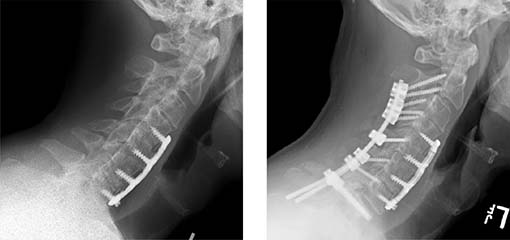

When surgery is needed, our spine surgeons work with you to create a plan using the least invasive techniques possible. Our team offers minimally invasive spine surgery (MISS), which allows for smaller incisions, less scar tissue, and same-day surgeries in many cases.

- Cervical myelopathy

- Chin on chest syndrome

- Ossification of the posterior longitudinal ligament (OPLL)